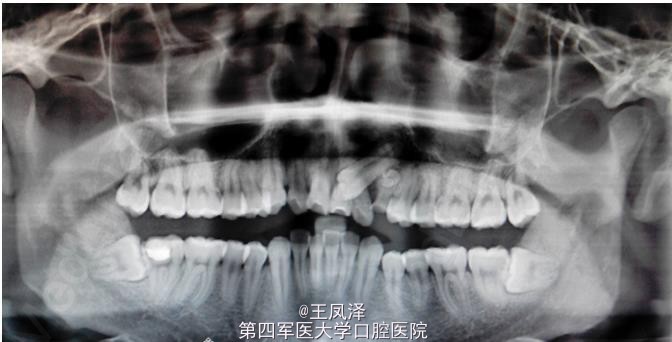

者、董x、男、21岁。主诉:上前牙松动一个月。专科检查:21松动Ⅲ°,22松动Ⅱ°。乳Ⅲ滞留。21腭侧牙龈处可见23的牙尖暴露。x光片检查:23牙冠位于21、22之间。乳Ⅲ牙根少许吸收,其根方有一致密团块,大小如黄豆。临床诊断:23埋伏阻生、21、22压迫性吸收、乳Ⅲ滞留伴牙瘤。处理意见:建议拔除21、22.正畸牵引23.+拔除乳Ⅲ+摘除其下方的牙瘤。患者觉得正畸牵引23时间长,不考虑正畸。因此,处理建议为:拔除21、22、23、乳Ⅲ及摘除其下方牙瘤。两个月后行义齿修复。